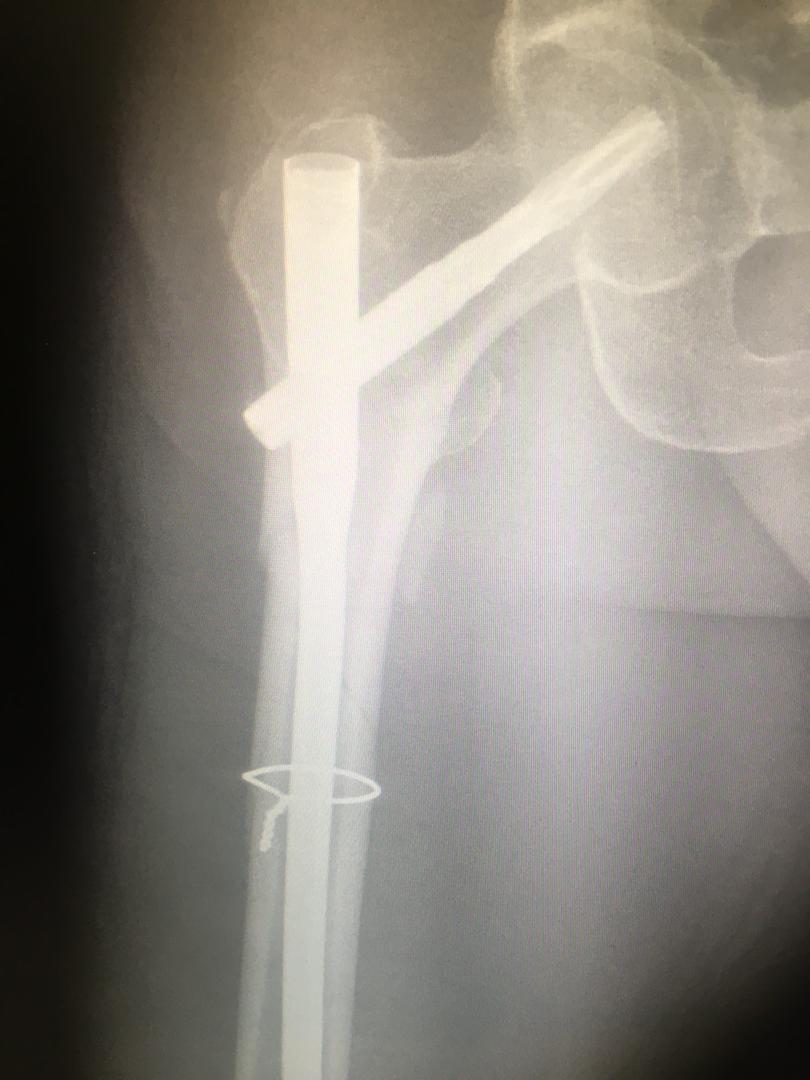

اقای 21 ساله با شکستگی له شده ی ساق و زانو که جراحی شد و بهبودی کاملاقای 50 ساله با قطع شدگی و له شدگی مچ پاله شدگی و قطع مچ پا6 ماه پس از جراحی ترمیمی و پیوندشکستگی مفصل ران و فمورجراحی فیکساسیون

اقای 50 ساله با شکستگی خرد شده ی ران که جراحی و بهبودی کامل